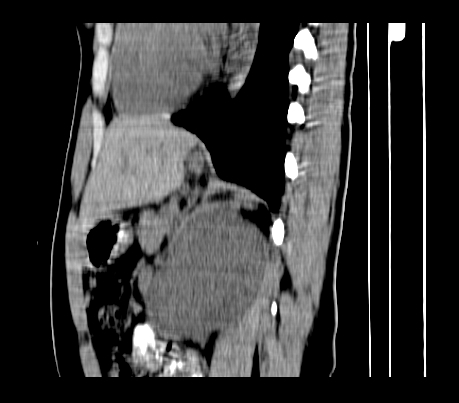

标题: CT23915:女 20岁 全身长疙瘩三年 今日多体位查 看看吧 [打印本页]

标题: CT23915:女 20岁 全身长疙瘩三年 今日多体位查 看看吧

腹部平扫